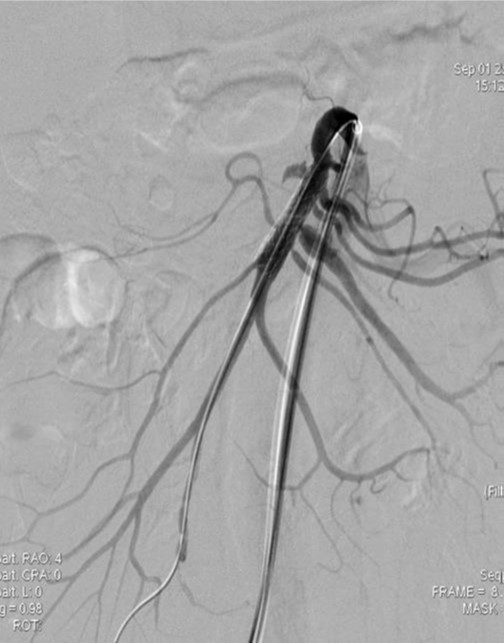

2009년 3월 복부 CT에서 SMA 기시부 하방 2cm 부위부터 5cm 길이의 편심성 혈전이 관찰되고 있으며 혈전이 있는 부위의 동맥 직경이 커져 있음(Fig. 1). 대동맥이나 분지 동맥에 동맥경화증의 소견은 관찰되지 않으며 심장초음파 및 심전도 검사에서 혈전이나 심방 세동은 없었음. CT 소견과 증상을 기준으로 spontaneous isolated SMA dissection으로 진단하였으며 창자의 허혈 소견이 보이지 않고 통증도 악화되지 않아 보존적 치료를 하였음. 2009년 6월 추적 CT에서 false lumen내 대부분의 혈전은 소실되었으나 SMA 기시부 5cm 하방 부위에는 국소적 혈전을 동반한 saccular pseudoaneurysm이 관찰됨. 2009년 8월 시행한 추적 CT에서 pseudoaneurysm의 직경이 2mm 증가함 (Fig. 2). 2009년 9월 시행한 혈관 조영술에서 saccular pseudoaneurysm이 SMA 기시부 5cm 하방부위에 관찰되며 SMA의 국소적 협착이 관찰됨 (Fig. 3). 스텐트와 코일을 이용한 혈관 내 치료 후 시행한 혈관 조영술에서 SMA의 국소적 협착과 pseudoaneurysm은 소실됨 (Fig. 4). 시술 3개 월 후 시행한 추적 CT에서 pseudoaneurysm은 완전히 소실되었으며 SMA는 정상소견을 보임(Fig. 5).

Right femoral artery를 천자하여 superior mesenteric artery에 7-Fr guiding catheter(Cordis, FL, USA)를 위치시킨 후 시행한 혈관 조영술에서 SMA dissection 부위 true lumen의 협착과 동반된 pseudoaneurysm이 관찰됨, 협착된 SMA의 true lumen내에 6mm 직경, 29mm 길이의 balloon expandible stent(Genesis, Cordis, FL, USA)를 설치함.

스텐트 설치 후 협착은 소실되었으나 pseudoaneurysm은 소실되지 않고 크기만 작아짐. 스텐트의 철망을 통해 2.4 Fr microcatheter(Progreat, Terumo, Tokyo, Japan)를 pseudoaneurysm내에 위치시킨 다음 5mm microcoil (Cook, Bloomington, IN) 1개를 삽입함. 시술 후 시행한 혈관 조영술에서 SMA 협착과 pseudoaneurysm은 완전히 소실되었으며 추적 관찰기간 동안 재발 소견은 보이지 않음.

Fig. 4. A

Fig. 4. A. The size of psedoaneurysm is decreased, but still noted after stent placement in the superior mesenteric artery.

Fig. 4. B

B. After insertion of microcatheter in the sac of pseudoaneurysm through the mesh of stent, a 5mm diameter microcoil is placed in the sac.

Fig. 4. C

C. Completion angiography shows improvement of pseudoaneurysm and stenosis in the superior mesenteric artery.